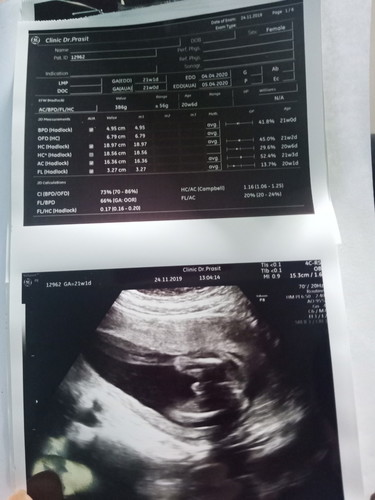

สอบถามหน่อยค้ะ ว่าได้เพศไหน พอดีไม่ได้ถามหมอ?

โผล่มาแบบยื่นมาน่าจะผ.ชนะคะแม่ บ้านนี้ก็ยื่นแบบนี้ตอน14วีคแล้วก็ชัดขึ้นเรื่อยๆค่ะ😂

ใบสรุปการอ่านไม่ได้แจ้งว่าเพศอะไรค่ะ แต่ดูจากรูปน่าจะผู้ชาย

ในใบซาวบอกว่าเป็นผู้หญิงค่ะ แต่ดูจากรูปเหมือนผู้ชายมากกว่า

หญิงค่ะ เห็นขาวๆ เหมือนเครื่องหมายเท่ากับ

ชายคะที่แม่เห็นนี่น่าจะเปนไข่น้องนะ😅😅😅

น่าจะชายนะคะ เหมือนกับของที่บ้านเลยค่ะ

ผู้หญิงรึป่าวค่ะ...เห็นหมอพิมพ์ไว้ว่า female

น่าจะ ชาย ค่ะ รอหมอฟันธงอีกทีนะคะ

เหมือนจะ ช. นะคะ เห็นจู๋โผล่ด้วย